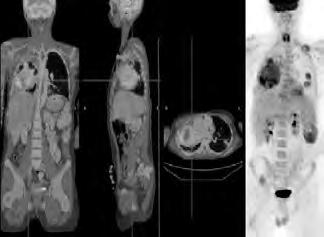

2.6.4 Radionuklidové metody (Daniela Chroustová) 35